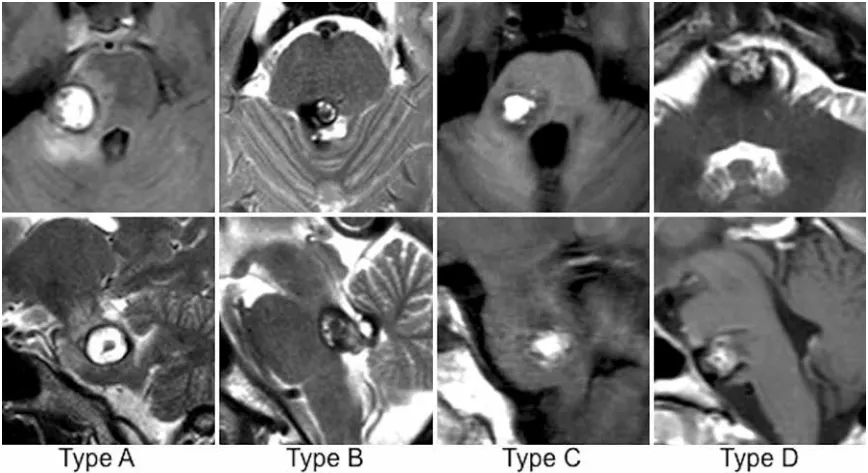

在这项研究中,巴教授团队将脑桥海绵状血管瘤系统划分为四个类型,并依据病变位置与解剖特征,为每种类型制定了针对性的手术入路选择策略。研究的重点比较集中在两种常用入路之间——脑桥后外侧入路与脑桥后内侧入路。

数据结果揭示了两种入路之间显著的差异。在77名同时符合两种入路条件的患者中,选择后外侧入路的54例患者,术后永久性外展神经麻痹发生率仅3.7%,面神经麻痹发生率仅1.9%;而选择后内侧入路的23例患者,上述两项并发症的发生率均为21.7%。两组间的差距之大,充分说明了手术入路选择对神经功能保护的决定性影响。

纵观135名患者的整体结果,术后永久性外展神经和面神经功能缺损的发生率分别被控制在5.9%和5.2%的较低水平。患者改良Rankin量表评分从术前的1.6分改善至随访时的1.0分,表明绝大多数患者在病灶获得完整切除的同时,神经功能也得到了切实保护。

巴教授这一系列研究的价值不仅在于将手术致残率压缩至极低水平,更在于构建了一套系统的病变分型与个体化入路选择体系,让这项曾被视为"禁区手术"的操作,真正走向了精准可控。